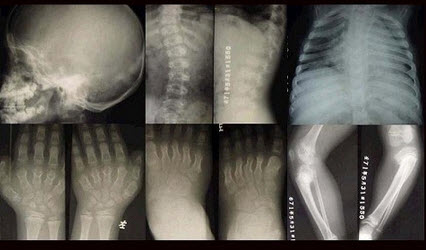

女,3岁,身体发育异常,如图所示,最可能的诊断为()

A.成骨不全

B.粘多糖病

C.软骨发育不全

D.佝偻病

E.侏儒症